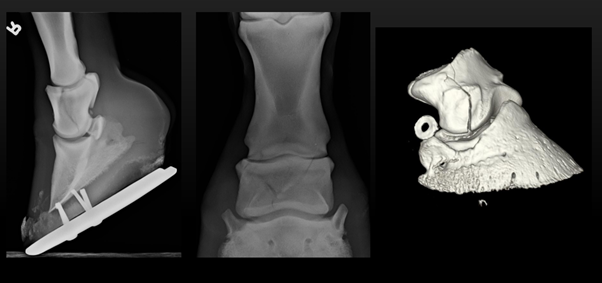

- The CT moves 360 degrees around the region of interest, taking multiple x-rays at various angles

- The images are then reconstructed to create a 3D image of an individual structure.

- No superimposition as with 2d x-rays – can reformat images in alternate cross-sectional planes/3D

Reconstructed 3D image of the hoof